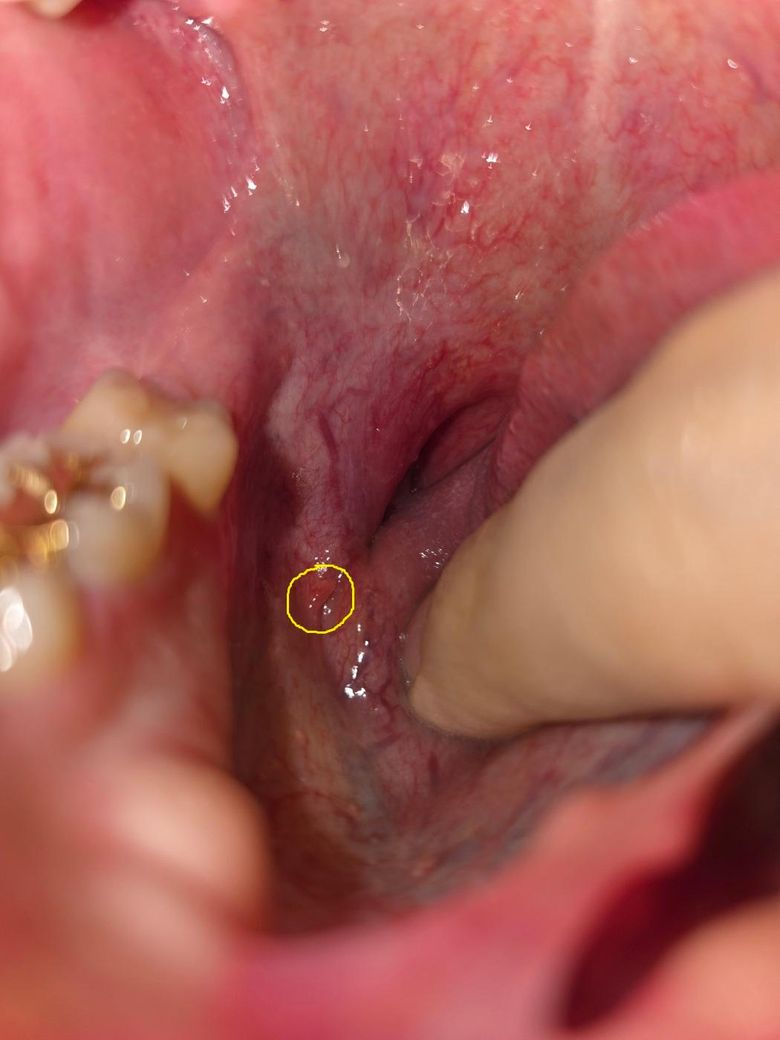

입안에 돌기 같은게 낫는데 이게 뭘까요?

입 안쪽 혀 오른쪽 깊숙한 곳에 돌기 같은 것이 나서 몇일째 없어지질 않고 있는데 무엇인지 알 수 있을까요?

통증은 없는데 갑자기 이런게 생기니깐 신경 쓰이네요

• 1번 째 사진

사진으로는 정확한 진단 불가능하며 병원 방문하셔서 직접 육안으로 진료 보셔야 합니다

입안에 돌기 같은 것이 나타난 경우, 여러 가지 원인이 있을 수 있습니다. 가장 흔한 원인 중 하나는 혀에 발생하는 미각선으로, 이는 보통 특별한 통증 없이 발생할 수 있으며 시간이 지나면서 자연스럽게 사라집니다. 또 다른 가능성은 구내염이나 아프타성 구내염일 수 있습니다. 이는 작은 혹처럼 보일 수 있고, 통증 없이 발생할 수 있지만 시간이 지나면서 염증이 생길 수 있어요. 또한 설암이나 다른 치과적인 문제가 원인일 수도 있지만, 이 경우는 드물며, 지속적인 통증이나 크기가 커지는 경우에는 병원에서 정확한 진단을 받는 것이 중요합니다.

현재로서는 통증이 없다고 하셨으니 심각한 상태는 아닐 수 있지만, 이상한 돌기나 혹이 계속해서 사라지지 않거나 변형되는 경우에는 치과나 구강내과 전문의에게 진료를 받는 것이 좋습니다. 이를 통해 정확한 원인을 파악하고 필요한 치료를 받을 수 있을 듯 해요